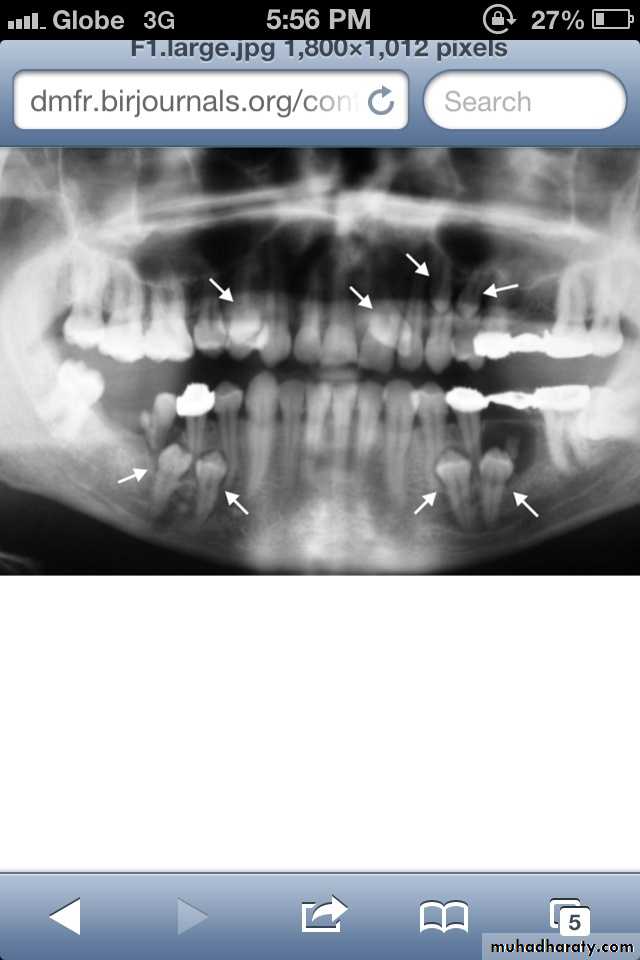

Dentin dysplasia, type I. panoramic & periapical films of the same case show the short and poorly developed roots, obliterated pulp chambers and root canals, and periapical inflammatory lesions.